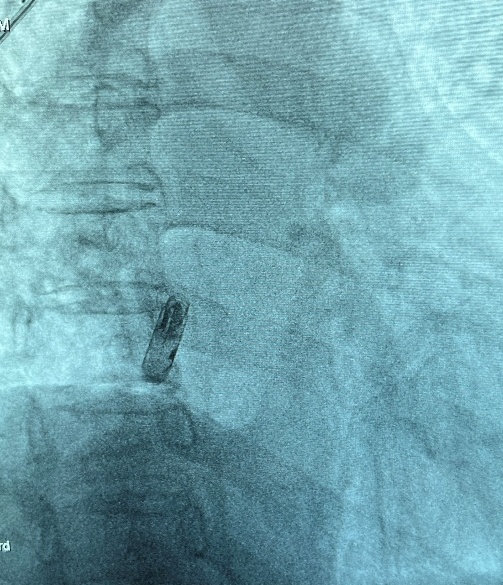

手术在局部麻醉下顺利开展。陈爱兰教授团队在患者大腿根部的股静脉建立微创通道,使用猪尾导管进行右心耳造影作为参考,成功将心房无导线起搏器送至右心耳基底部这一目标位置并进行保护套筒造影确认,分别在LAO30度和RAO30度下验证无导线起搏器的位置,进行Mapping测试,阈值2.0V/0.4ms,感知2.7mV,阻抗310欧(血液阻抗280欧),参数满意、旋入无导线起搏器。旋入1.5圈后进入对接栓模式,做张力测试验证稳定性没问题后顺利释放!最终参数,阈值3.5V/0.4ms(2.75V/1.0ms)、感知1.3mV,阻抗380欧。患者心跳瞬时恢复60次每分钟,“如获心生”。